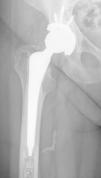

We present a series of cases recorded in our centre of migration of cement through a tributary vein or artery of the femoral diaphysis while performing partial and total cemented hip prostheses (Fig. 1).

ResultsWe found a total of 14 patients whose postoperative radiography showed a cement arteriovenogram. They were all female, with an average age at surgery of 77.6 years (63–89 years). The mean height was 159 cm and the BMI was 27.3. Of the surgeries, 64.3% (9) were performed for coxarthrosis and 35.7% (5) for intracapsular femoral fractures. Laterality was left in 42.9% of the cases (6) and right in 57.1% (8). The stems used in the arthroplasty were metaphyseal anchoring stems in 71.4% (1 with MBA’s Furlong® model and 9 with Zimmer-Biomet’s F40™ model) and diaphyseal anchoring stems in 28.6% (4 with Stryker’s Exeter™ model).

The average length of the cement arteriovenogram was 26.3 mm, 100% of which was located on the posterior-internal face of the femur, at 154 ± 10 mm distal to the greater trochanter and at 17 ± 10 mm proximal to the tip of the stem. Dividing the femur into sixths, 35.7% (5) showed leakage in the proximal second sixth and 64.3% (9) in the proximal third sixth.

The constancy of the postero-internal location and at a distance that could correspond to the anatomical position of this femoral nutrient bundle should lead us to consider extrusion of the cement towards the veins or arteries that make up the bundle (Fig. 2). Likewise, the linear morphology of the radiographic image suggesting the vessel being occupied by cement, venous valves being observed, differs completely from that produced by a cortical defect or a periprosthetic fracture (Fig. 3), which would result in an irregular image without tubular appearance or the presence of valves.13